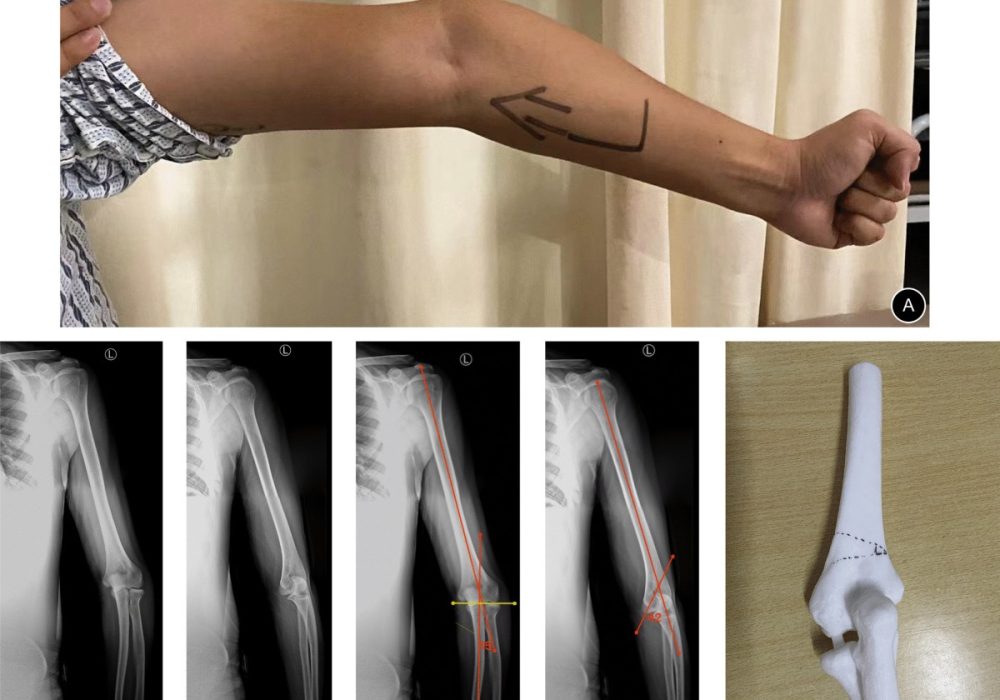

Cubitus varus, often called the “gunstock deformity,” is characterized by an inward angulation of the forearm relative to the humerus when the arm is extended and supinated. In this condition, the forearm deviates towards the midline of the body, resulting in a varus (medial) angulation at the elbow.

This deformity is most commonly a sequela of malunited supracondylar fractures of the distal humerus in children. It can also result from growth disturbances or improper healing after trauma.

• X-rays: Anteroposterior (AP) and lateral views of the elbow are essential.

• In cubitus varus, the humero-ulnar angle is decreased or negative.

• Measurement of carrying angle: The angle between the long axis of the humerus and the forearm.

• CT scan or 3D imaging: May be used in complex deformities for preoperative planning.